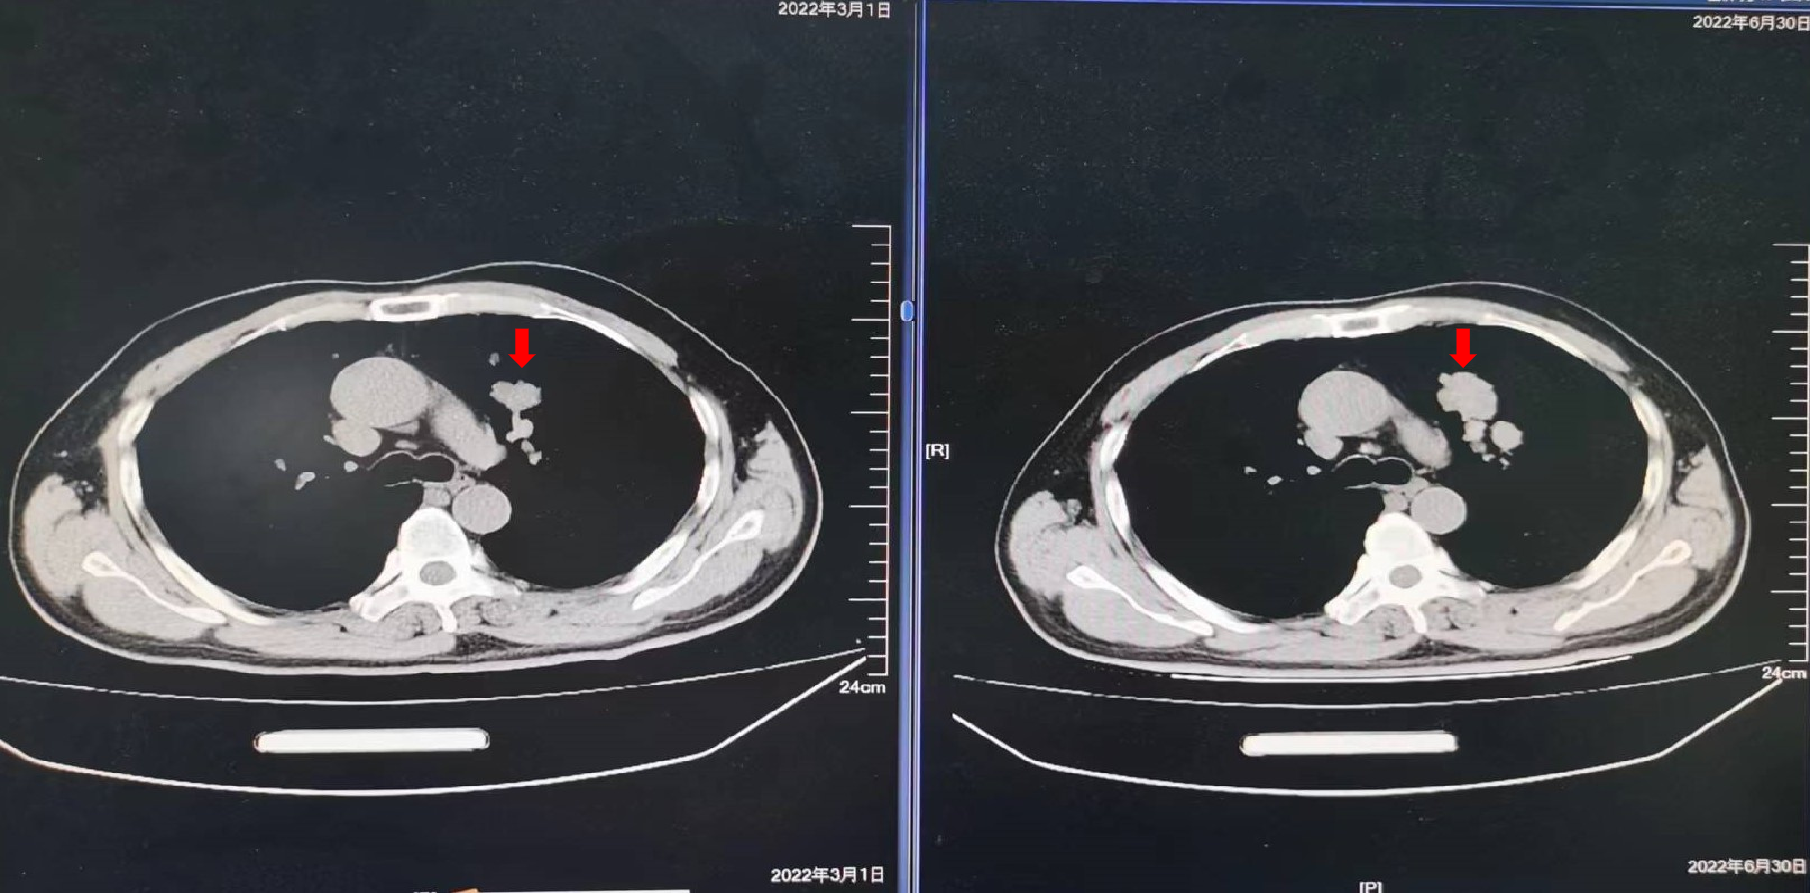

2019年10月16日:复查影像学检查提示新发肺转移,建议贝伐珠单抗,患者拒绝,继续XELOX方案化疗2周期,卡培他滨口服1周期,疗效为PD。

2021年5月27日:开始口服曲氟尿苷替匹嘧啶片(TAS-102)55mg每日2次 d1-5,d8-12,Q4W配合信迪利单抗免疫治疗。

疗效评价:SD,患者右腹股沟肿胀疼痛明显减轻,停用止痛药,PFS时间为10个月,主要不良反应为Ⅱ度骨髓抑制。